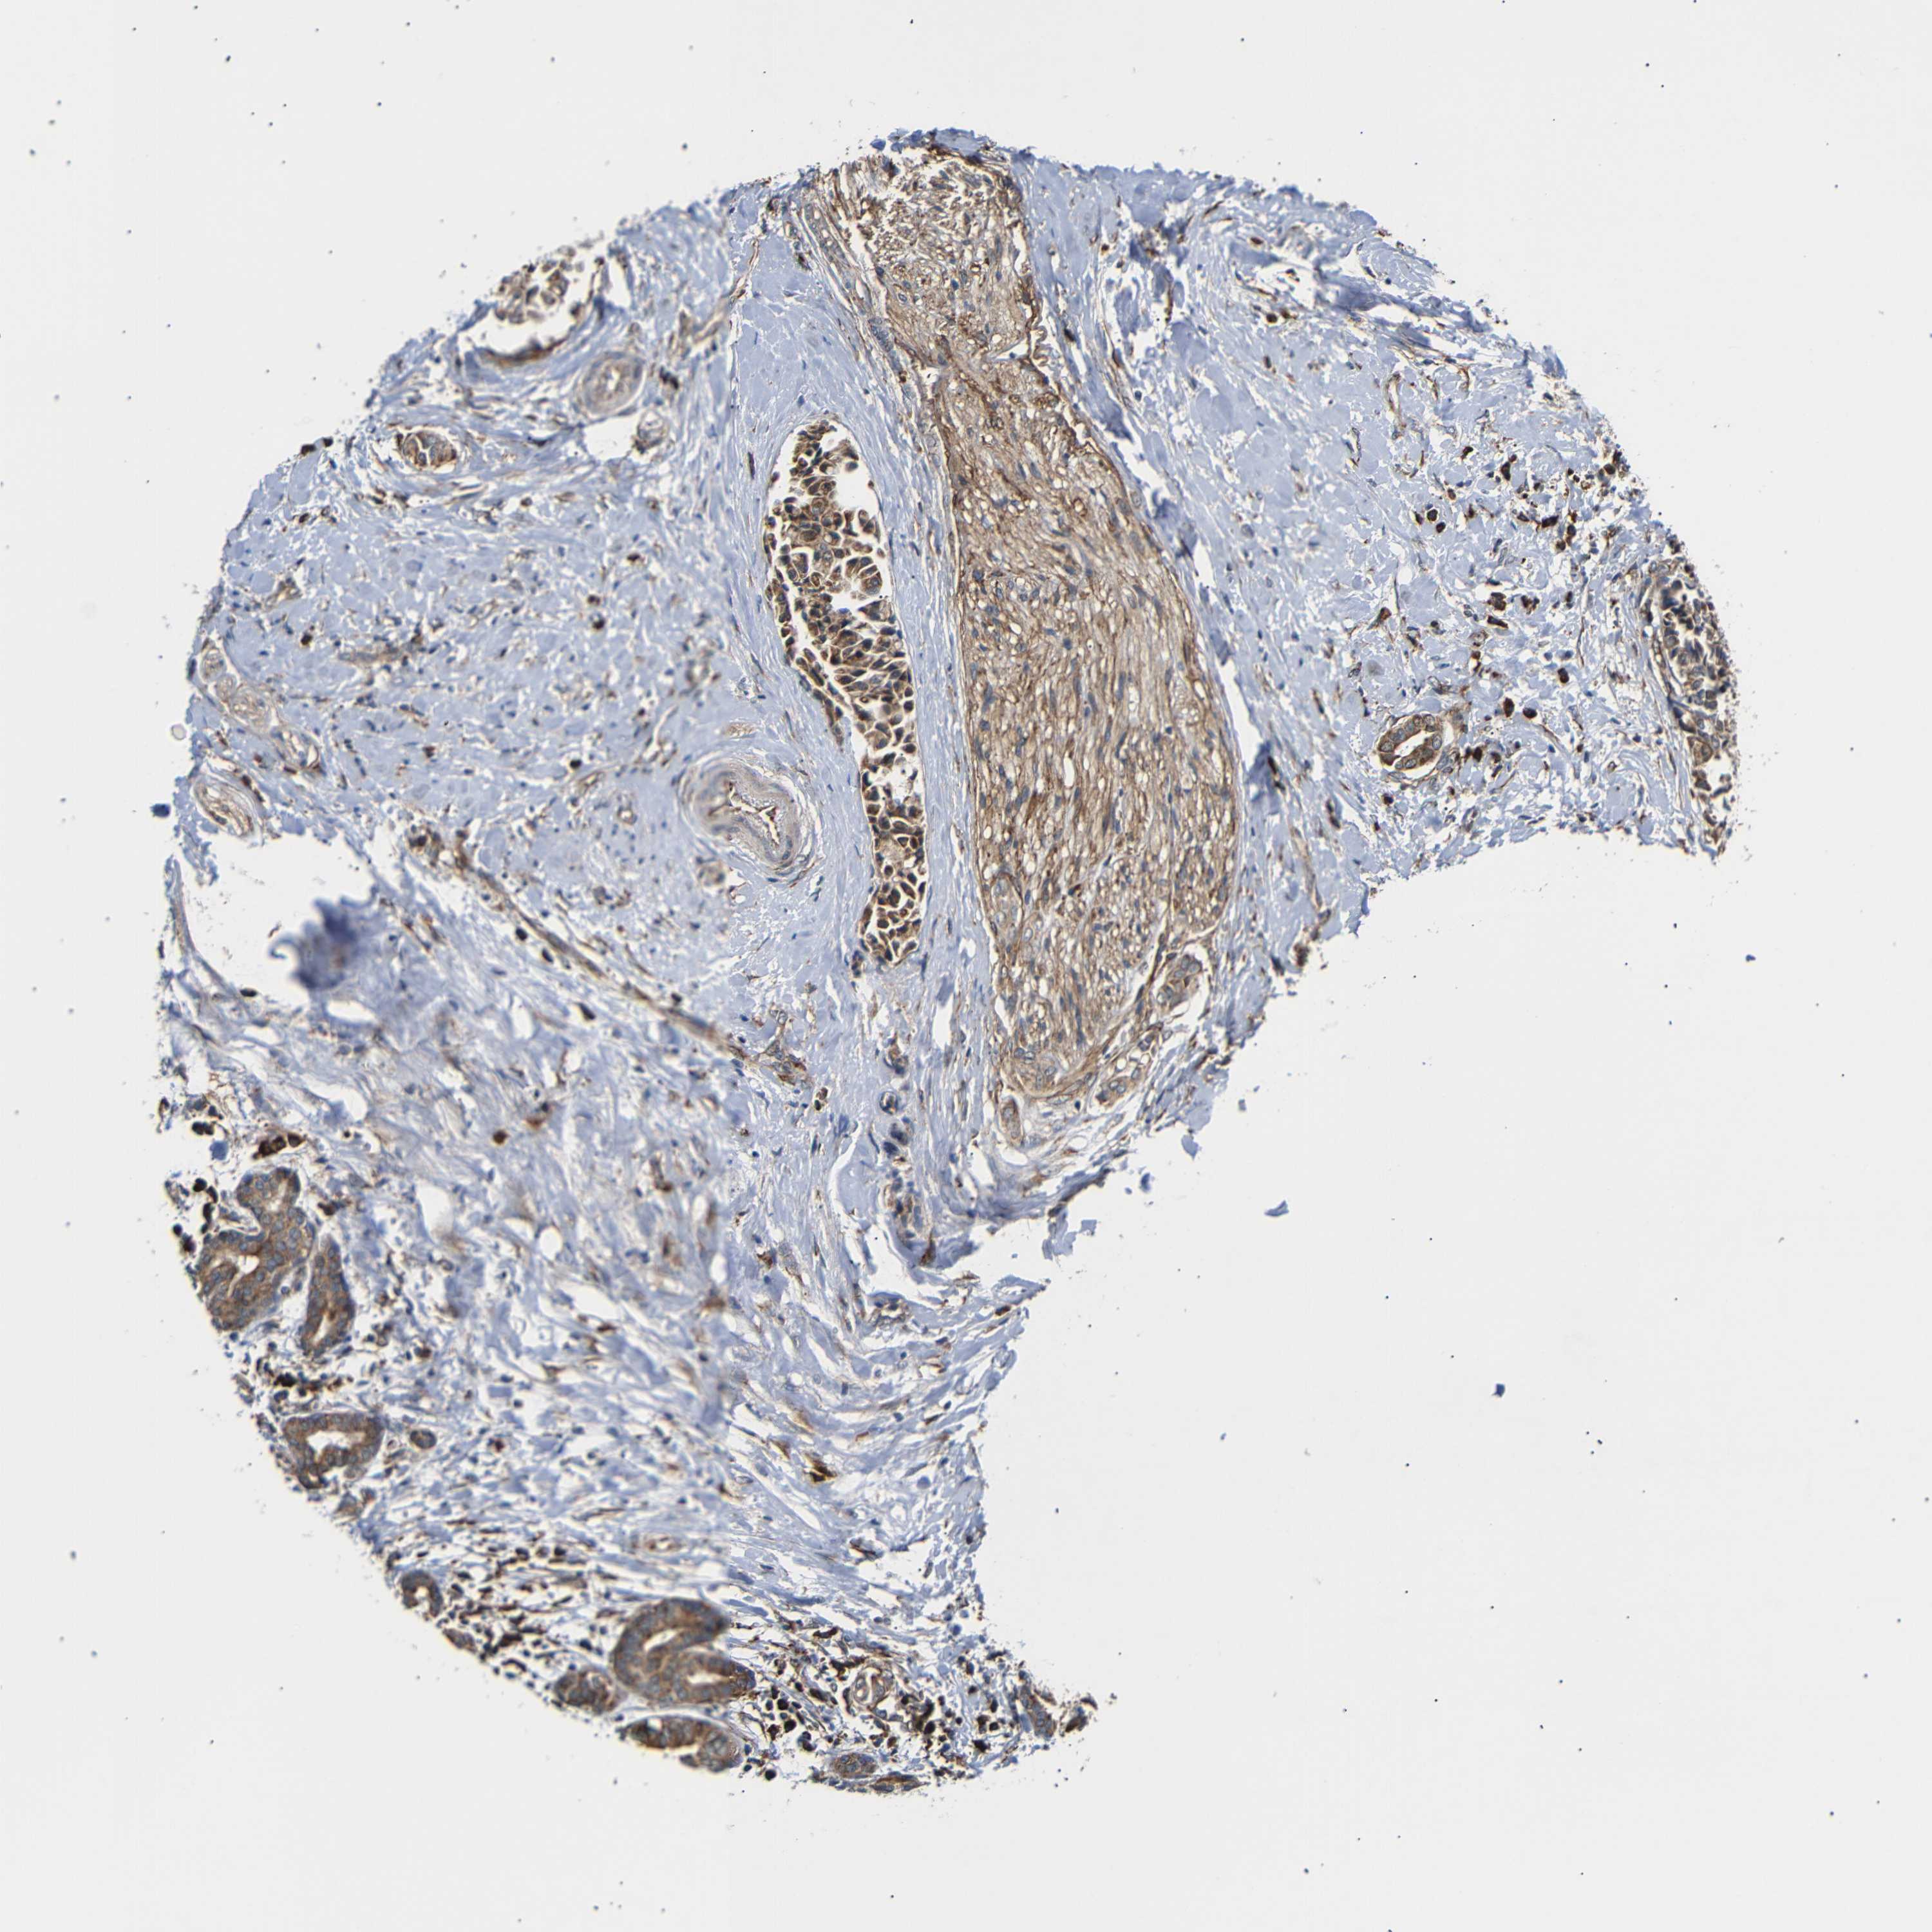

HEAD AND NECK CANCER - Protein expressioni

A mouse-over function shows sample information and annotation data. Click on an image to view it in a full screen mode. Samples can be filtered based on level of antibody staining by selecting one or several of the following categories: high, medium, low and not detected. The assay and annotation is described here.

Antibody stainingi

Antibody staining in the annotated cell types in the current human tissue is reported as not detected, low, medium, or high, based on conventional immunohistochemistry profiling in selected tissues. This score is based on the combination of the staining intensity and fraction of stained cells.

Each image is clickable and will lead to virtual microscopy that enables deeper exploration of all samples and also displays staining intensity scores, fraction scores and subcellular localization as well as patient and tissue information for each sample.

Antibody HPA014030

Staining

High

Medium

Low

Not detected

Intensity

Strong

Moderate

Weak

Negative

Quantity

>75%

75%-25%

<25%

None

Location

Nuclear

Cytoplasmic/membranous

Cytoplasmic/membranous,nuclear

Squamous cell carcinoma, NOS